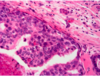

What is this image Herpes Simplex 1 Herpes Simplex 2 HPV 6 HPV 16 HPV 18

**Herpes Simplex 1** Herpes Simplex 2 HPV 6 HPV 16 HPV 18